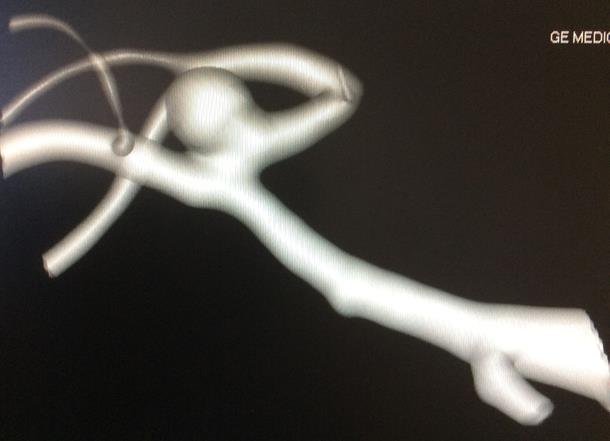

Un aneurisma cerebral consiste en la formación de un saco o dilatación en la pared de una arteria del cerebro. Su tamaño puede oscilar desde uno o dos milímetros hasta aneurismas gigantes, mayores de 2,5 cm. Generalmente no ocasionan síntomas salvo que alcancen un tamaño considerable y compriman estructuras vecinas.

El diagnóstico del aneurisma cerebral no roto se realiza mediante pruebas de imagen específicas del árbol vascular cerebral:

• Angio-resonancia magnética

• Angio-TAC

• Arteriografía cerebral

La arteriografía cerebral fue durante años la prueba de referencia, aunque se trata de una técnica invasiva que requiere cateterismo arterial. En la actualidad, el angio-TAC y la angio-resonancia permiten diagnosticar y caracterizar los aneurismas cerebrales con una sensibilidad comparable, sin necesidad de procedimientos invasivos.

En el contexto de una hemorragia subaracnoidea, el diagnóstico del aneurisma cerebral roto suele realizarse mediante angio-TAC craneal, tras la detección inicial del sangrado en el TAC simple.